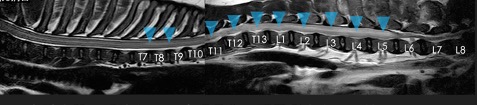

進行性脊髄軟化症は重度の脊髄障害に続発して生じる、致死的な病態です。 椎間板ヘルニアグレード5や交通事故などによる椎体骨折、椎体脱臼などにより生じた脊髄障害部を中心に、頭尾側方向に脊髄の壊死が進行することで強い疼痛や呼吸障害を呈し死に至る怖い病気です。 椎間板ヘルニアグレード5では約10〜15%が発症すると言われており、さらにフレンチブルドッグでは約30%とさらに確率が高いと報告されています。 以前は治療法が確立しておらず、発症した場合には安楽死が推奨されていましたが、近年、有効な外科治療が報告され大幅に救命率が上昇しました。 手術は、広範囲片側椎弓切除術と硬膜切開術という術式を組み合わせて行います。進行性脊髄軟化症を生じている脊髄は、炎症により腫れており、これがさらなる悪化につながります(図1:進行性脊髄軟化症のMRI)。そのため、上記の手術により脊髄にかかる圧を減圧することで進行を抑制します。 進行性脊髄軟化症状は発症してしまった場合、時間との勝負となります。脊髄の壊死が呼吸障害や前肢の麻痺を生じる領域まで達してしまった場合には、手術で進行がとまったとしてもQOLが保つことができないため安楽死が推奨されます。そのため、呼吸障害がでるまでに診断し治療することが重要となります。ただし、この手術は救命を目的としたものとなりますので、通常の椎間板ヘルニアの手術と異なり、脊髄機能の改善は認められませんので、排便や排尿、皮膚の管理などの介護が生涯必要となります。 当院でも積極的に実施している手術となりますので、軟化症と診断された、疑いがあると診断された飼い主様はいつでもご相談ください。 神経科 武藤

脊髄が進行性脊髄軟化症を強く疑わられるMRI(青矢頭領域)